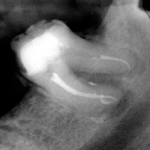

Sécher le système canalaire. Réaliser l’obturation canalaire, le plus souvent à l’aide de gutta-percha chauffée ou froide, liée aux parois dentinaires avec un ciment canalaire.